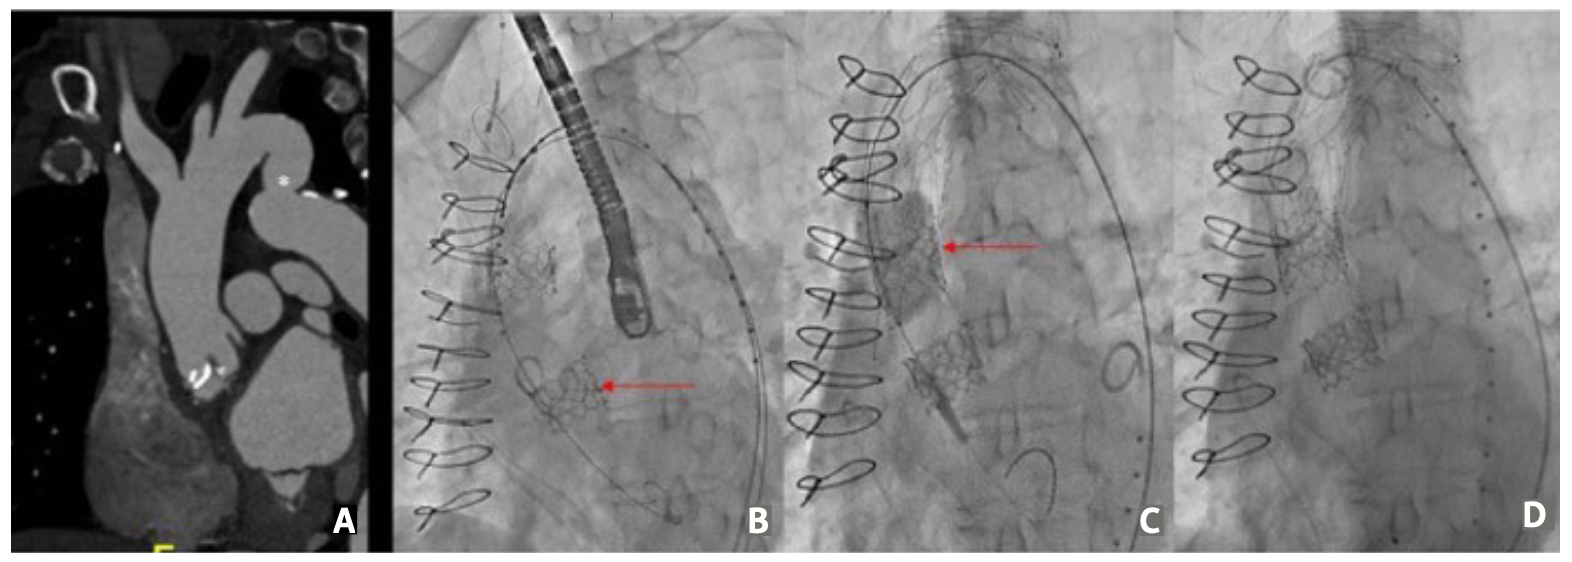

Echocardiography demonstrated severe bioprosthetic AV stenosis (mean gradient, 50 mm Hg; aortic valve area, 0.84 cm2) and moderate AV regurgitation. Valve-in-valve transcatheter aortic valve replacement with a Sentinel cerebral protection device (Boston Scientific) was recommended. Preoperative computed tomography scan showed dilated aortic root and descending aorta with evidence of pseudocoarctation (Figure 1A).

A 23-mm Edwards Sapien 3 valve (Edwards Lifesciences) was deployed. Before the valve was fully expanded, it embolized into the aortic root due to stored tension (Video 1). Attempts to insert the valve inside the prosthetic valve were unsuccessful. An additional 23-mm S3 valve was advanced through the embolized valve and was successfully deployed (Figure 1B). In order to stabilize the first S3 valve, an uncovered 36- x 120-mm dissection stent was implanted via an extra-stiff Lunderquist wire (Cook Medical). A TriLobe balloon (Gore) was advanced over the wire and inflated within the embolized valve to ensure appropriate stent apposition (Figure 1C). A final angiogram showed good flow into the aorta and good stent apposition (Figure 1D).